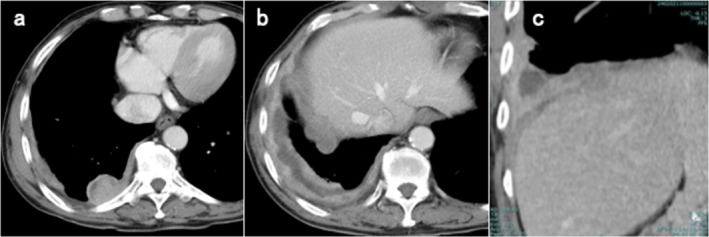

Abstract Image